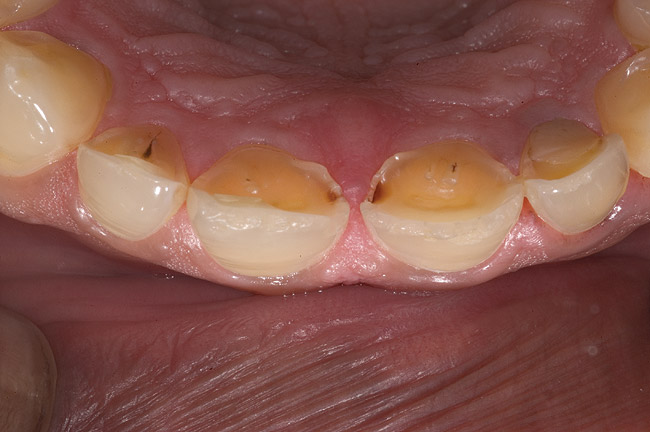

Figure 6  1:1 view demonstrating severe loss of tooth structure due to palatal erosion.

Figure 6

Figure 7  Palatal surface showing loss of form due to enamel dissolution.

Acid dissolves the palatal enamel of upper anteriors, thus exposing the underlying dentin. This makes teeth appear higher in chroma and leads to hypersensitivity as well as supraeruption of opposing incisors. Clinically, this restricts the space needed to restore lost palatal tooth structure (Figure 1 and Figure 2).